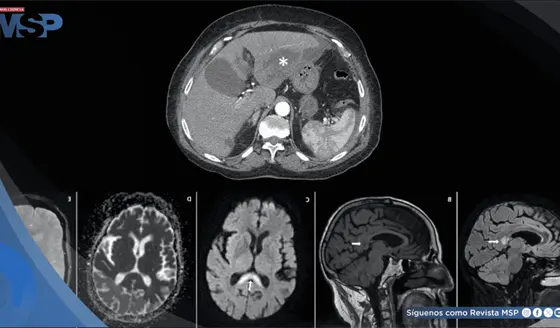

El intenso dolor torácico no fue una recaída ni metástasis, sino un daño óseo provocado por la reirradiación. Los huesos, debilitados por la radioterapia previa y la reirradiación, estaban perdiendo su capacidad de curarse adecuadamente.